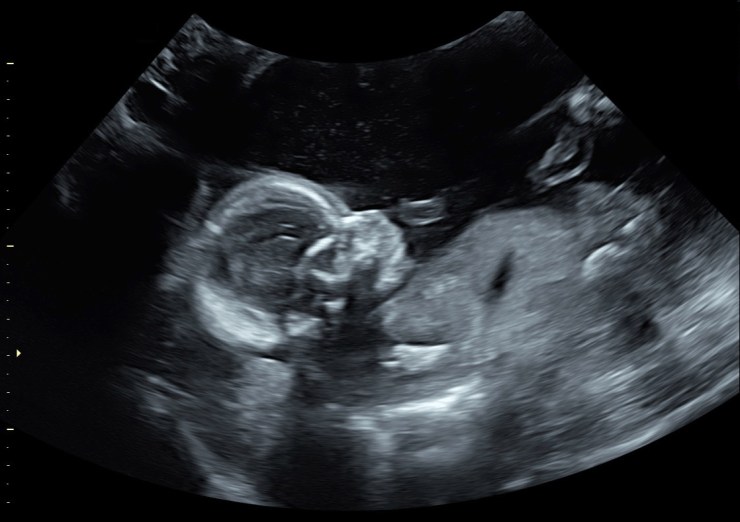

aw dreamy, we got to see our babies face (and body, feet, arms and lips!)

we went to Seattle Ultrasound Center and had a great tech, who im sure we were her favorite can of the day #duh, and it was just thrilling to finally see our baby! omg there’s a real baby in there! like so real and so fun. this was our first ultrasound, typically people would have a few by now, but we didnt really need confirmation of pregnancy or estimation of due date…so the 20 week scan was our first necessary one. not a blob, but a baby! so it was amazing to see a face, 2 arms, 2 legs, toes and fingers, kidneys…..the heart! all that.

one of the coolest parts was the first sight we got when she put the scanner on me, was the straight on view of lips and eyes! the lips looked beautiful and big like dads and then she scanned up to the eyes and the sockets looked huge, like mine! that was so fun to see possibly resemblance in the womb! who knows, maybe we’re seeing what we wanted….but the straight on view was so cool compared just to the profile view.

getting to see the lips and eyes straight on!